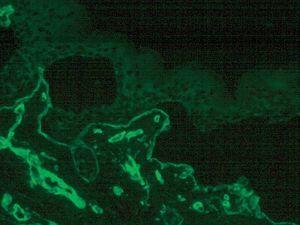

La inmunofluorescencia puso de manifiesto una ampolla subepidérmica. Los anticuerpos monoclonales contra las integrinas α5 y β4 y el BP180 tiñeron el techo de la ampolla. Los anticuerpos contra el colágeno IV (fig. 5) y colágeno VII tiñeron el suelo de la ampolla pero la tinción con anticuerpo GB3 (laminina 5) fue negativa.

Fig. 5.--Inmunofluorescencia con anticuerpos anti-colágeno tipo IV en el suelo de la ampolla.

Una alternativa en el diagnóstico de las epidermólisis ampollosas es el mapeo antigénico por inmunofluorescencia, usando anticuerpos contra las proteínas estructurales de la región de la membrana basal tales como el antígeno del penfigoide ampolloso (BP180), la laminina y los colágenos tipo IV y VII. El conocimiento de la localización ultraestructural de dichos antígenos permite determinar el plano de hendidura. Como en nuestro caso, en la EAJ-H el mapeo antigénico muestra los colágenos tipo IV y VII en el suelo de la ampolla y el BP180 en la cara inferior del techo de la misma. Como es lógico, en la EAJ-H la tinción con anticuerpo antilaminina 5 (anticuerpo monoclonal GB3) es negativa o muy débil 12,13.